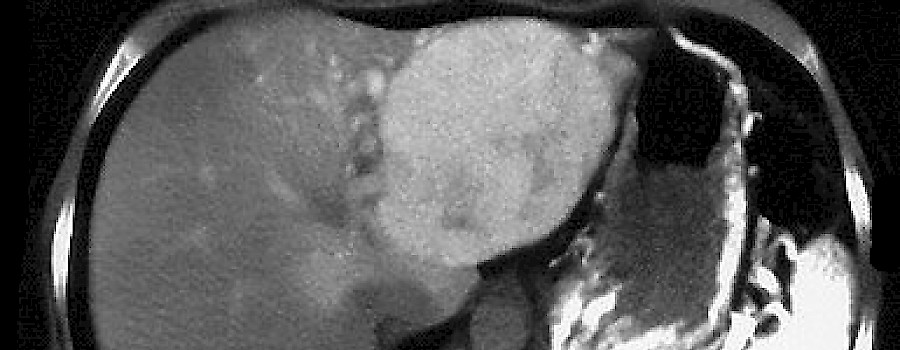

Die seltene fokale noduläre Hyperplasie (FNH) ist eine gutartige Wucherung in der Leber und betrifft häufig Frauen (75 %). Es wird ein Zusammenhang mit der Einnahme von Kontrazeptiva vermutet.